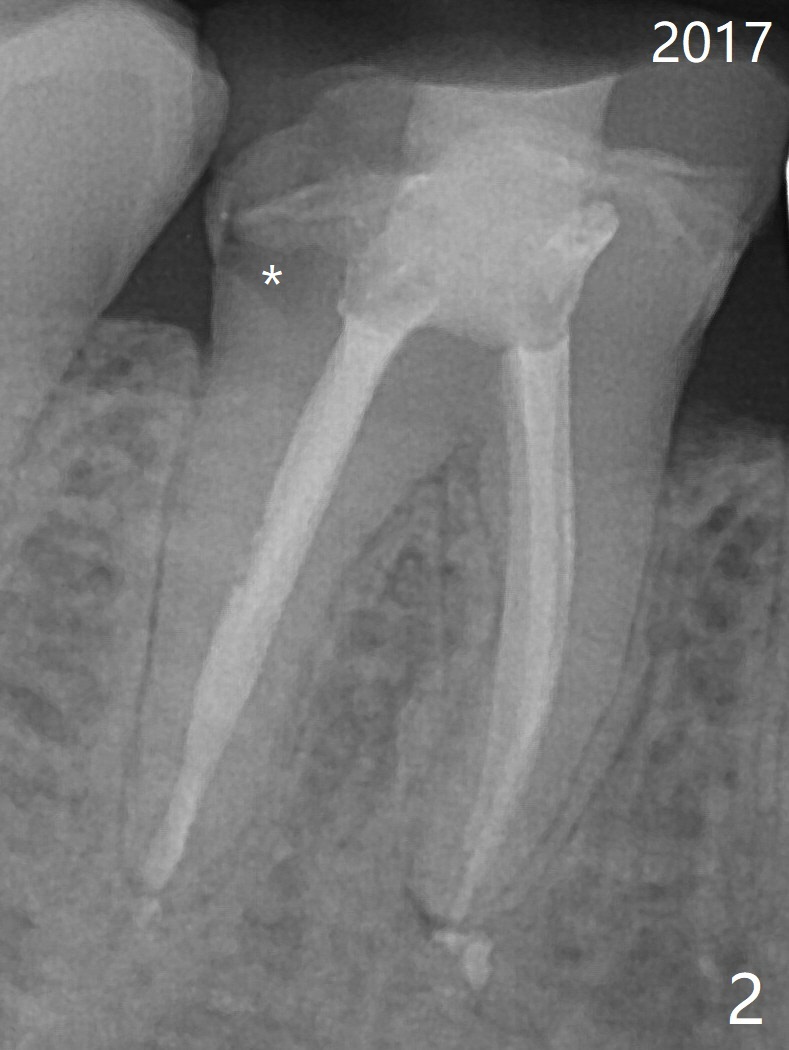

55岁女特别害怕牙科治疗,6年前右下6根分叉以及根尖阴影(图一),根管治疗后3年(图二(阴影消失))才回来做牙冠,现在牙冠因为继发性龋齿而脱落(图三(根尖阴影重现)),病人同意导板即刻种植(图四)。用外科手机去除中隔冠方牙根,完成钻洞后拔除牙根,放入植体。